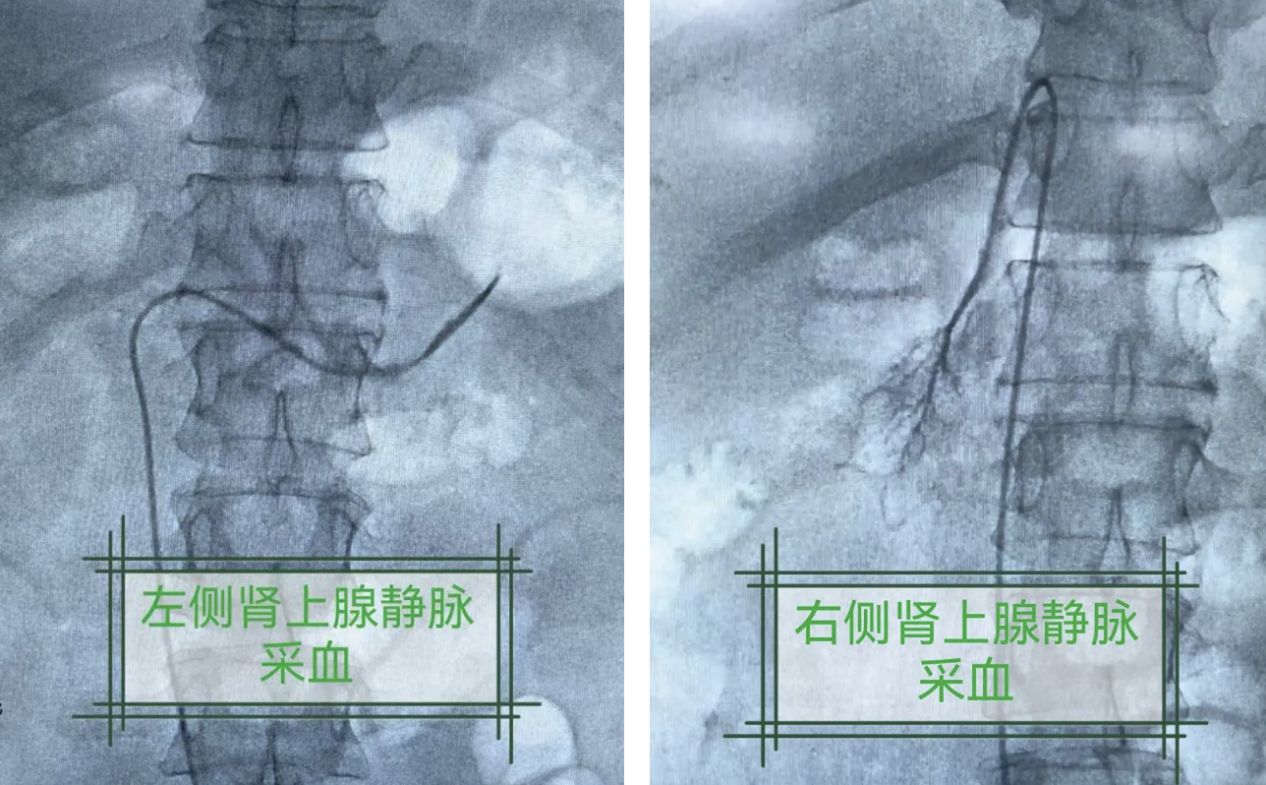

他们采用肾上腺静脉采血(AVS)技术,在介入引导下通过微创导管,分别采集左右肾上腺静脉的血液,检测两侧肾上腺静脉醛固酮、皮质醇等激素水平。结果揭晓:患者虽然为双侧肾上腺肿瘤,但右侧肾上腺才是“优势分泌侧”,是导致高血压和低血钾的元凶。